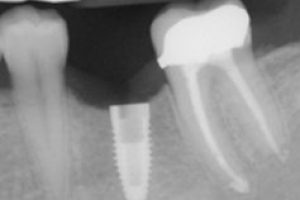

In a perfect world, adults would hang on to all (or most) of their natural teeth well into old age. Unfortunately, tooth loss is still a major problem for …